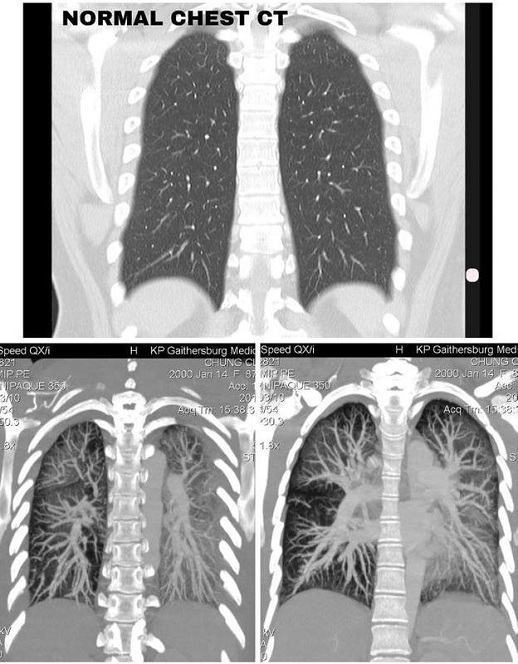

Một cô gái Mỹ gốc Á đã được gia đình cho nhập viện vì sốt nhiều ngày không khỏi. Sau khi kiểm tra các bác sĩ mới thấy lá phổi của bệnh nhân bị trắng đục. Được biết cô gái này đã hút thuốc lá điện tử trong 1 thời gian dài. Claire Chung 19 tuổi, phổi bị tổn thương nặng nề do hút thuốc lá điện tử, với các mô có màu trắng đục thay vì đen như bình thường.

Ngày 6/1, Claire Chung đã chia sẻ hình ảnh chụp CT phổi của mình, mục đích kêu gọi thanh thiếu niên dừng hút thuốc lá điện tử.

Hình ảnh CT cho thấy phổi Claire tổn thương nặng nề, các mô bị hủy hoại hoàn toàn, ống phế quản có biểu hiện viêm nghiêm trọng.

Phổi của người bình thường (trên) và phổi của Claire Chung (dưới)

"Kết quả chụp CT phổi, vô cùng đáng lo. Phổi của người khỏe mạnh khi chụp CT sẽ có màu đen, còn tôi, ở tuổi 19, cả hai phổi toàn màu trắng đục", Claire nói.